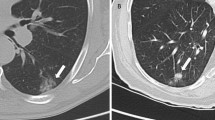

Images were reviewed by three independent observers blinded to patient details and each other’s assessments using Hermes GOLD™ (Hermes Medical Solutions; Stockholm, Sweden). The observers included one nuclear medicine physician, one nuclear medicine clinical fellow in training and one oncology clinical fellow PhD student with 30, 3 and 1 years of experience in nuclear medicine image analysis, respectively. Regions of interest including primary tumour and metastatic lesions, including lymph nodes and normal tissue references (lung, liver and blood pool), were identified with CT correlation. Using a freehand manual technique, the maximum count for regions of interest (ROImax) was recorded from 1- and 2-h SPECT images (n = 42) for each patient. ROImax was chosen as ROImean could be affected by differences in the manual segmentation and is more likely to be affected by the partial volume effect. In addition, the method using ROImax was previously shown to correlate with IHC [11]. Freehand ROImax was recorded for normal lung in the right upper lobe (or contralateral upper lobe if pathology present) for calculation of tumour-to-lung (T:L) ratio and for blood pool within the aortic arch for calculation of tumour-to-blood pool (T:BP) ratio. To evaluate if rule-based approaches improved consistency of scoring of normal tissue references, ROImax was also recorded using a standardised 3-cm-diameter sphere for normal lung at the level of the aortic arch and carina, and the liver at the level of the gastroesophageal junction (GOJ) on axial view. Examples of image analysis are provided in Fig. 1. To determine intraobserver agreement, the two independent observers with least experience (one nuclear medicine and one oncology clinical fellow) repeated their calculations for all measured regions blind to their initial measurements following a 42-day period.

Image analysis using ROImax scoring of [99mTc]NM-01 SPECT/CT of: primary left lower lobe tumour, IHC PD-L1 65% (a), freehand; unaffected lung tissue freehand (b) and using a 3-cm sphere at level of the aortic arch (c); blood pool reference tissue (d); liver reference tissue freehand (e) and using a 3-cm sphere at the axial level of the gastroesophageal junction (f)